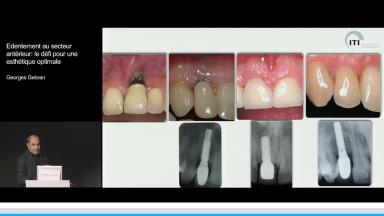

A partir de la description des facteurs de risque esthétique du bloc incisivo-canin maxillaire, de la présence d’os et de gencive autour des implants, le conférencier présente une succession de cas cliniques décrivant ses procédures chirurgicales et prothétiques.

- de déterminer le bon timing de chirurgie implantaire post extractionnelle

- de réfléchir sur la préservation à moyen-long terme de l’os autour des implants